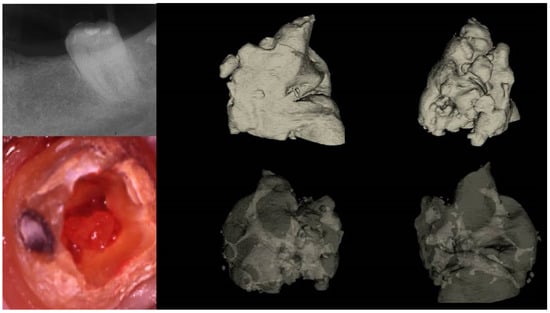

Figure 11.

(I) (A) Preoperative panorax focused on the impacted right maxillary canine, revealing a large lesion. (B) Two-year follow-up panorax after the surgical removal of the lesion revealing healing. (C,D) Periapical radiographs reveal recurrent disease 6 years after the surgical intervention. Notice that the maxillary canine was brought in occlusion with orthodontic treatment, but the canal was rendered radiographically blocked. (E,F) CBCT axial slices evaluate the magnitude of the periapical lesion and the root canal calcification of the maxillary canine. (II) (A,B) Clinical microscopic image from two different angles of the previously initiated access cavities. Notice the gray spot indicating the calcified root canal orifice (yellow arrow). (C) Clinical image of the initial troughing of the calcified canal with a round long shafted bur (Munce bur). (D) EDM file during the buckling resistance activation test negotiation technique. (E) Clinical image of the calcified orifice after the first BRAT stroke. Canal negotiation with the 08 D-finder file is now possible. (III) A Preoperative periapical radiograph. (B) Periapical radiograph demonstrating the initial negotiation of an 08 D-finder after the first BRAT stroke. (C) Periapical length determination radiograph. (D) Postoperative radiograph. (E) One-year follow-up periapical radiograph. (F–H) Three-year follow-up cbct reveals complete healing of the periapical lesion (axial slices) (clinical images and radiographs courtesy of Dr. Chaniotis Antonis). Red arrows indicate the calcified canal location, and Yellow arrows indicate the impacted canine. The white circle is the projection of a nose piercing ring in the radiograph (not a symbol).